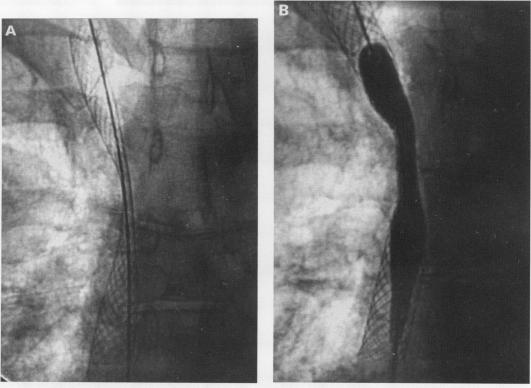

用于治疗上腔静脉阻塞的可扩张Wallstent支架。

Expandable Wallstent for the treatment of obstruction of the superior vena cava.

Palliative treatments for obstruction of the superior vena cava all have disadvantages. The use of a fine braided wire self expanding stent (Wallstent, Schneider (Europe) AG) in patients with malignant and benign causes of superior vena cava obstruction is reported.

METHODS

Five patients with obstruction of the superior vena cava were treated with balloon angioplasty of the stricture and the percutaneous insertion of an expandable Wallstent endoprosthesis across the site of the stricture. Four patients had advanced mediastinal malignancy previously treated by radiotherapy and one patient had fibrosing mediastinitis.

RESULTS

All patients experienced rapid symptomatic relief and, in three cases, complete palliation was achieved during survival times of seven weeks, nine weeks, and 24 weeks, respectively. Two surviving patients (with a recurrent thymoma and fibrosing mediastinitis) were free of symptoms when followed up at eight and nine months respectively.

CONCLUSIONS

Initial experience with the Wallstent endoprosthesis suggests that it is a valuable treatment alternative once conventional therapy has failed and gives rapid relief of symptoms to patients with obstruction of the superior vena cava.